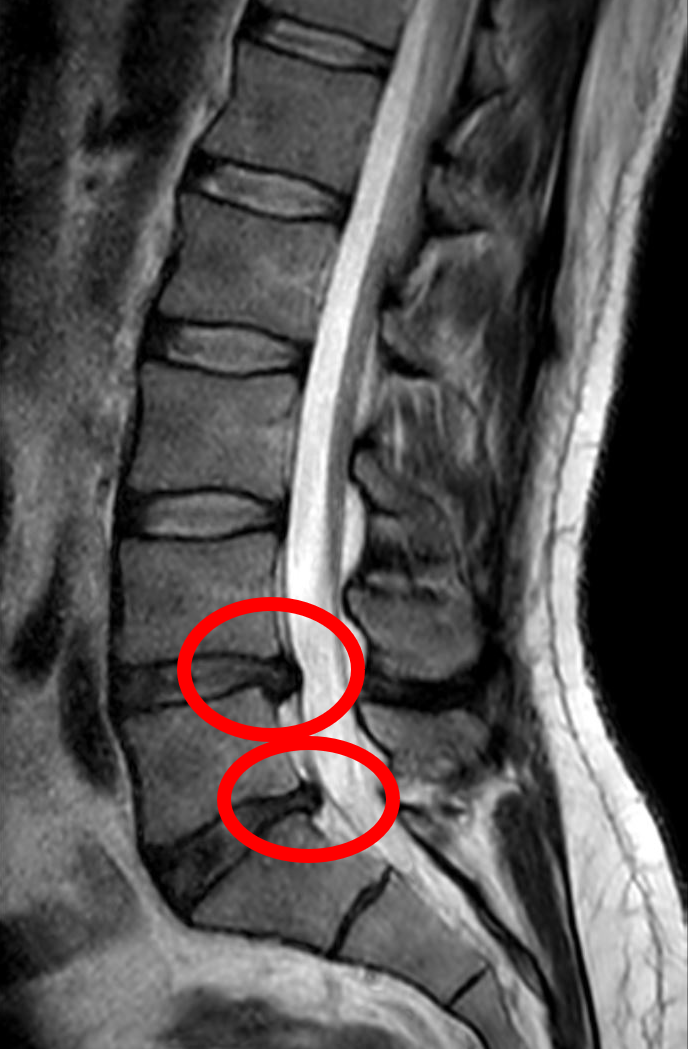

herniated nucleus pulposus (HNP)

when nucleus pulposus protrudes through fibrous cartilage layer into spinal canal, presses on spinal cord or nerves causing pain & numbness in extremities, most frequently L4-5

sciatica

low back pain radiating down the leg due to HNP pressing on the sciatic nerve

spondylolisthesis

forward movement vertebra on another, most common at L5-S1, due to spondylosis of pars or severe osteoarthritis

spondylolysis (lumbar)

separation of pars interarticularis (neck), most common at L4-5